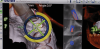

(14.) View of the dynamic 3D navigation system that was used to ensure ideal implant position.

Figure 14

(15.) The primary stability of the implant was assessed using RFA.

Figure 15

(16.) Because the implant’s ISQ value was above 65, immediate provisionalization could be performed with relative confidence.

Figure 16